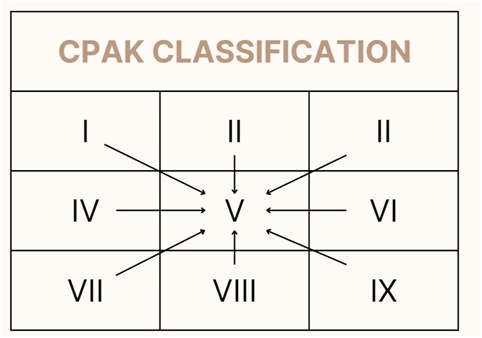

Recently, knee alignment has been found to fall into one of 9 categories and each patient who undergoes a knee replacement would fall in one of these 9 categories. The aim of conventional TKA was to get a perfect 180-degree alignment on standing view which would correspond to CPAK category V. In spite of good alignment, a section of patients arestill unhappy, and the hypothesis was that the change of CPAK category leads to dissatisfaction.

The principle of robotic TKA is to move patients towards better alignment but retaining the patient in the same CPAK category so that there is improvement in the patient’s functional outcome and satisfaction rates. This approach is to ensure that “One size fits all” approach is not undertaken and truly individualizing the care to each patient’s needs. This technique and philosophy were advocated by Dr. Johan Bellemens group in 2021 and now evidence is emerging that the CPAK philosophy helps patient achieve better satisfaction rates and our experience of more than 100 robotic knees are pointing towards the same outcome.